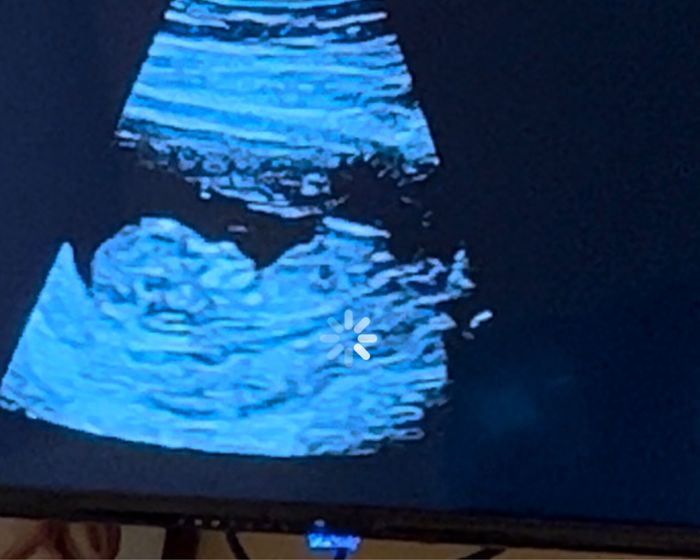

Nub theory, giochiamo un po’

Da Maria , Il 12 Agosto 2024 alle 19:10

Ciao ragazze, lunedì scorso ho fatto eco genetica a 11+5 ma bebè misurava 12 settimane, ho fatto dna fetale che dovrebbe arrivare questa settimana, ma nel frattempo per...